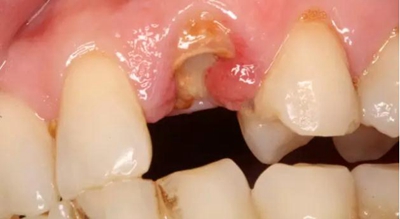

患者女性,55歲,3年前B3纖維樁+鑄瓷全冠修復(fù),一周前牙冠折斷,就診后,發(fā)現(xiàn)纖維樁根管口處折斷,周圍牙齦增生,建議患者行冠延長(zhǎng)手術(shù)。首先去除斷端的纖維樁。拍片示牙根長(zhǎng)度充足。于是開始冠延長(zhǎng)手術(shù)。

因?yàn)槭乔把?,故該患者將?lái)修復(fù)體邊緣必須為齦下,所以3個(gè)月后再行修復(fù)。以下為手術(shù)前照片。

以下為術(shù)中照片。